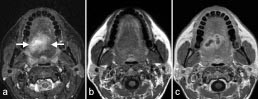

Selv om MR-teknikken kan fremstille samme anatomi med mange ulike bildekontraster, finnes det likevel patologiske prosesser med vevsegenskaper (f.eks. protontetthet, T1- og T2-verdi) som er så lik omgivende normalt vev at de derfor vanskelig lar seg detektere. Tilførsel av kontrastmiddel kan øke deteksjonen og også bidra til å karakterisere en lesjon. Det finnes mange ulike kontrastmidler for MR, men felles for de aller fleste er at de forkorter T1- og T2-relaksasjonen til omgivende protoner. Kontrastmidler som forkorter T1, fører til økt signal på T1-vektede bilder (positive kontrastmidler) (fig 9), mens kontrastmidler som forkorter T2, gir redusert signal på T2-vektede bilder (negative kontrastmidler).

Et enkelt indusert strømsignal inneholder ikke nok informasjon til at man ved hjelp av Fourier-transformasjon kan rekonstruere et bilde. Det kreves vanligvis mange strømsignaler og følgelig mange radiobølgepulser. De ulike gråtonene i bildet, bildekontrasten, er bestemt dels av de ulike vev som avbildes, dels av en rekke operatørbestemte parametere, som blant annet tidsintervallene mellom radiobølgepulsene og radiobølgenes styrke og varighet (som bestemmer flippvinkelen). Ved riktig valg av parametere kan ulike egenskaper ved vevene fremheves i bildet (3, 4). Man kan la gråtonene være bestemt av vevenes protontetthet, men også av andre egenskaper som for eksempel vevenes T1- eller T2-verdi. T1 er en tidsparameter som forteller hvor fort det reduserte overskuddet av parallelle protoner gjenoppbygges etter en radiobølgepuls. T2 er en annen tidsparameter som forteller hvor fort nettomagnetismen i x-y-planet forsvinner etter en radiobølgepuls. Begge disse parametrene er bestemt av fysiske og kjemiske egenskaper ved vevene og vil følgelig variere fra vev til vev (begge er relatert til molekylenes mobilitet). I et såkalt T1-vektet bilde er gråtonene langt på vei bestemt av forskjeller i T1 mellom vevene (kortest T1 gir kraftigst vokselmagnetisme og derfor lysest gråtone), og i et T2-vektet bilde er gråtonene bestemt av forskjeller i T2 (lang T2 gir kraftigst vokselmagnetisme og derfor lysest gråtone) (fig 8). Strømning i en væske vil også påvirke signalstyrken fra væsken. Blod i blodårer eller hjertet har således pga. sin bevegelse ofte en gråtone som gir god kontrast mot stasjonært vev, enten svart eller hvitt avhengig av den teknikken som brukes. Andre vevsavhengige parametere som bildemess

ig kan fremheves av ulike MR-teknikker, er diffusjon, perfusjon, blodets oksygeneringsgrad og temperatur.